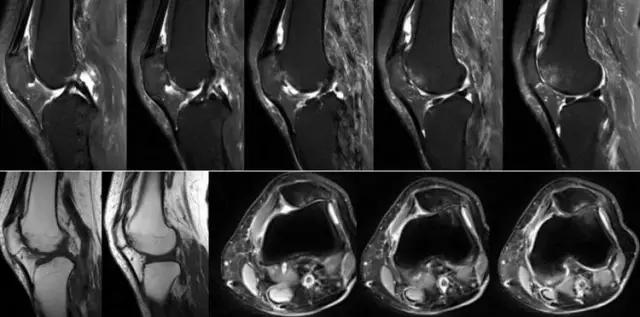

膝关节结核为侵袭性病变,会破坏膝关节的滑膜、软骨、骨等,所形成的寒性脓疡会顺着策划间隙流注,与其他疾病的表现不同。 病例:李XX,女,56岁,右膝关节疼痛逐渐加重8个月。手术及病理证实为膝关节结核。